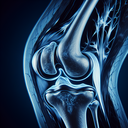

МРТ колінного суглобу

Звісно! МРТ (магнітно-резонансна томографія) колінного суглоба застосовується, щоб детально оцінити структури всередині суглоба. Це дослідження допомагає виявити різні проблеми, такі як: 1...